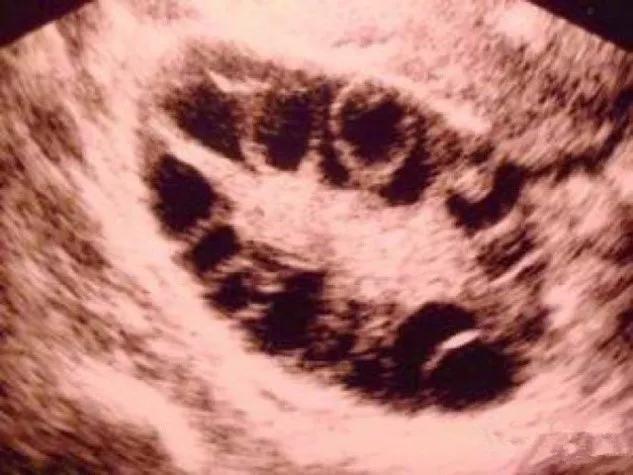

多囊卵巢综合征患者每个月有12个以上的卵泡发育,数量虽多但都长不大,没有发育成熟的优势卵泡,不能正常排卵。这些长不大的小卵泡们在B超下表现为小囊腔,我们称之为“卵巢多囊样改变”,即“多囊卵巢”。